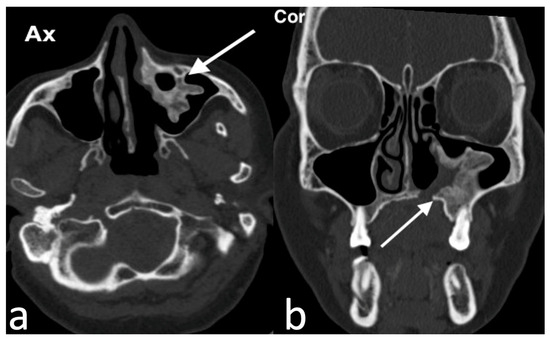

3.1.1. Septal Mucocele

3.1.2. Rinolith